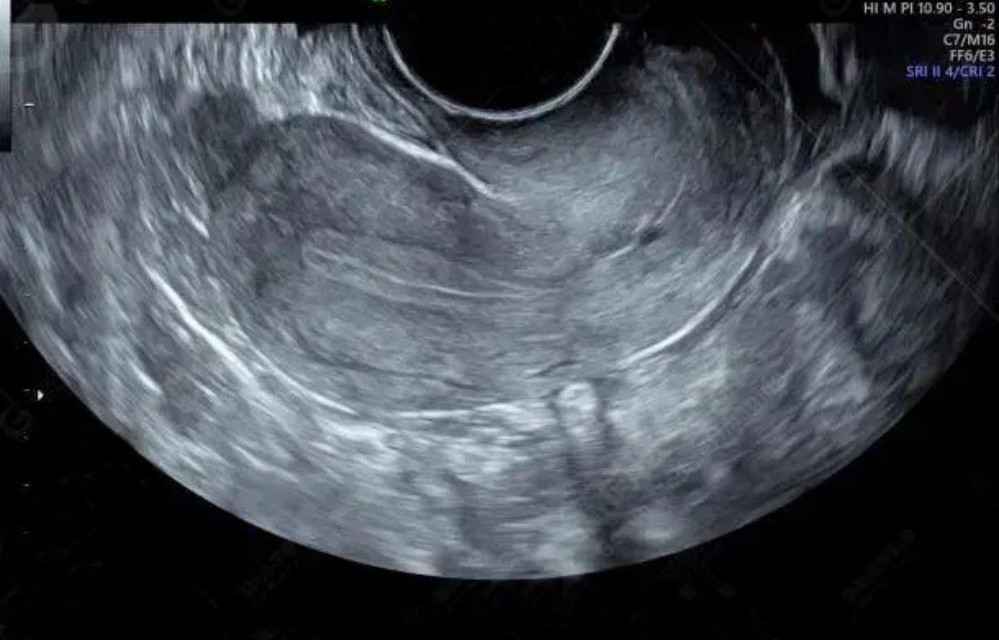

2018年6月13日杨华来到西京医院进行人工授精,医生将冷冻胚胎植入这个她也曾经住过的房子里。这已经是第五次尝试了,之前的手术都失败了。

这次受精卵着床了。 2018年6月27日杨华成功受孕。看到女儿忍受着一次次手术的折磨,杨华母亲露出了欣慰的笑容。

妊娠中晚期,胎儿出现生长受限,杨华又隔三差五地住院进行保胎治疗。医院的专家们也随时监测杨华与婴儿的健康状况,制定相应的免疫排斥用药等方案以确保胎儿正常发育。